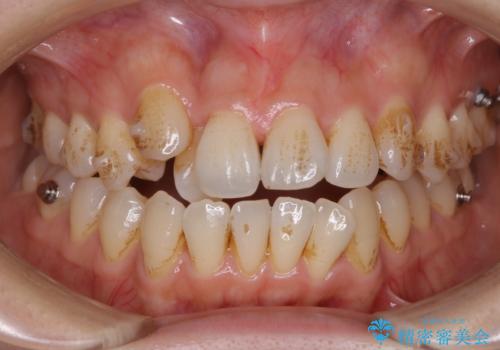

ワイヤー矯正中に歯の染め出し